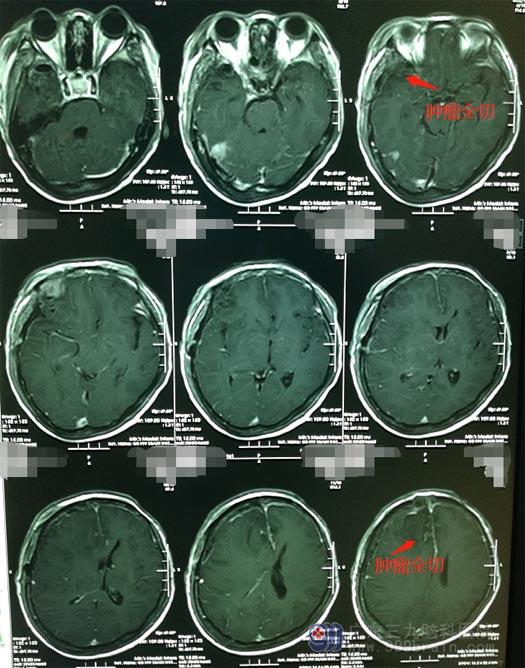

完善术前准备后,鲁明带领神经外五科治疗团队在全麻下行“右侧额部大脑镰旁、颞部多发脑膜瘤切除术”肿瘤位于大脑镰旁,大脑镰旁脑膜瘤起始于大脑镰,常埋入脑实质内并可向大脑镰两侧生长,肿瘤大多埋藏在大脑半球纵裂中,位置较深,所以暴露肿瘤位置成术中的难点;从周边逐步分离肿瘤,显微镜下予以分块全切除。手术顺利,重要神经及血管均没有损伤。

高阿姨麻醉苏醒后,即神志清楚、对答正确。在家人的悉心照料下,她恢复很快,不久就出院了。